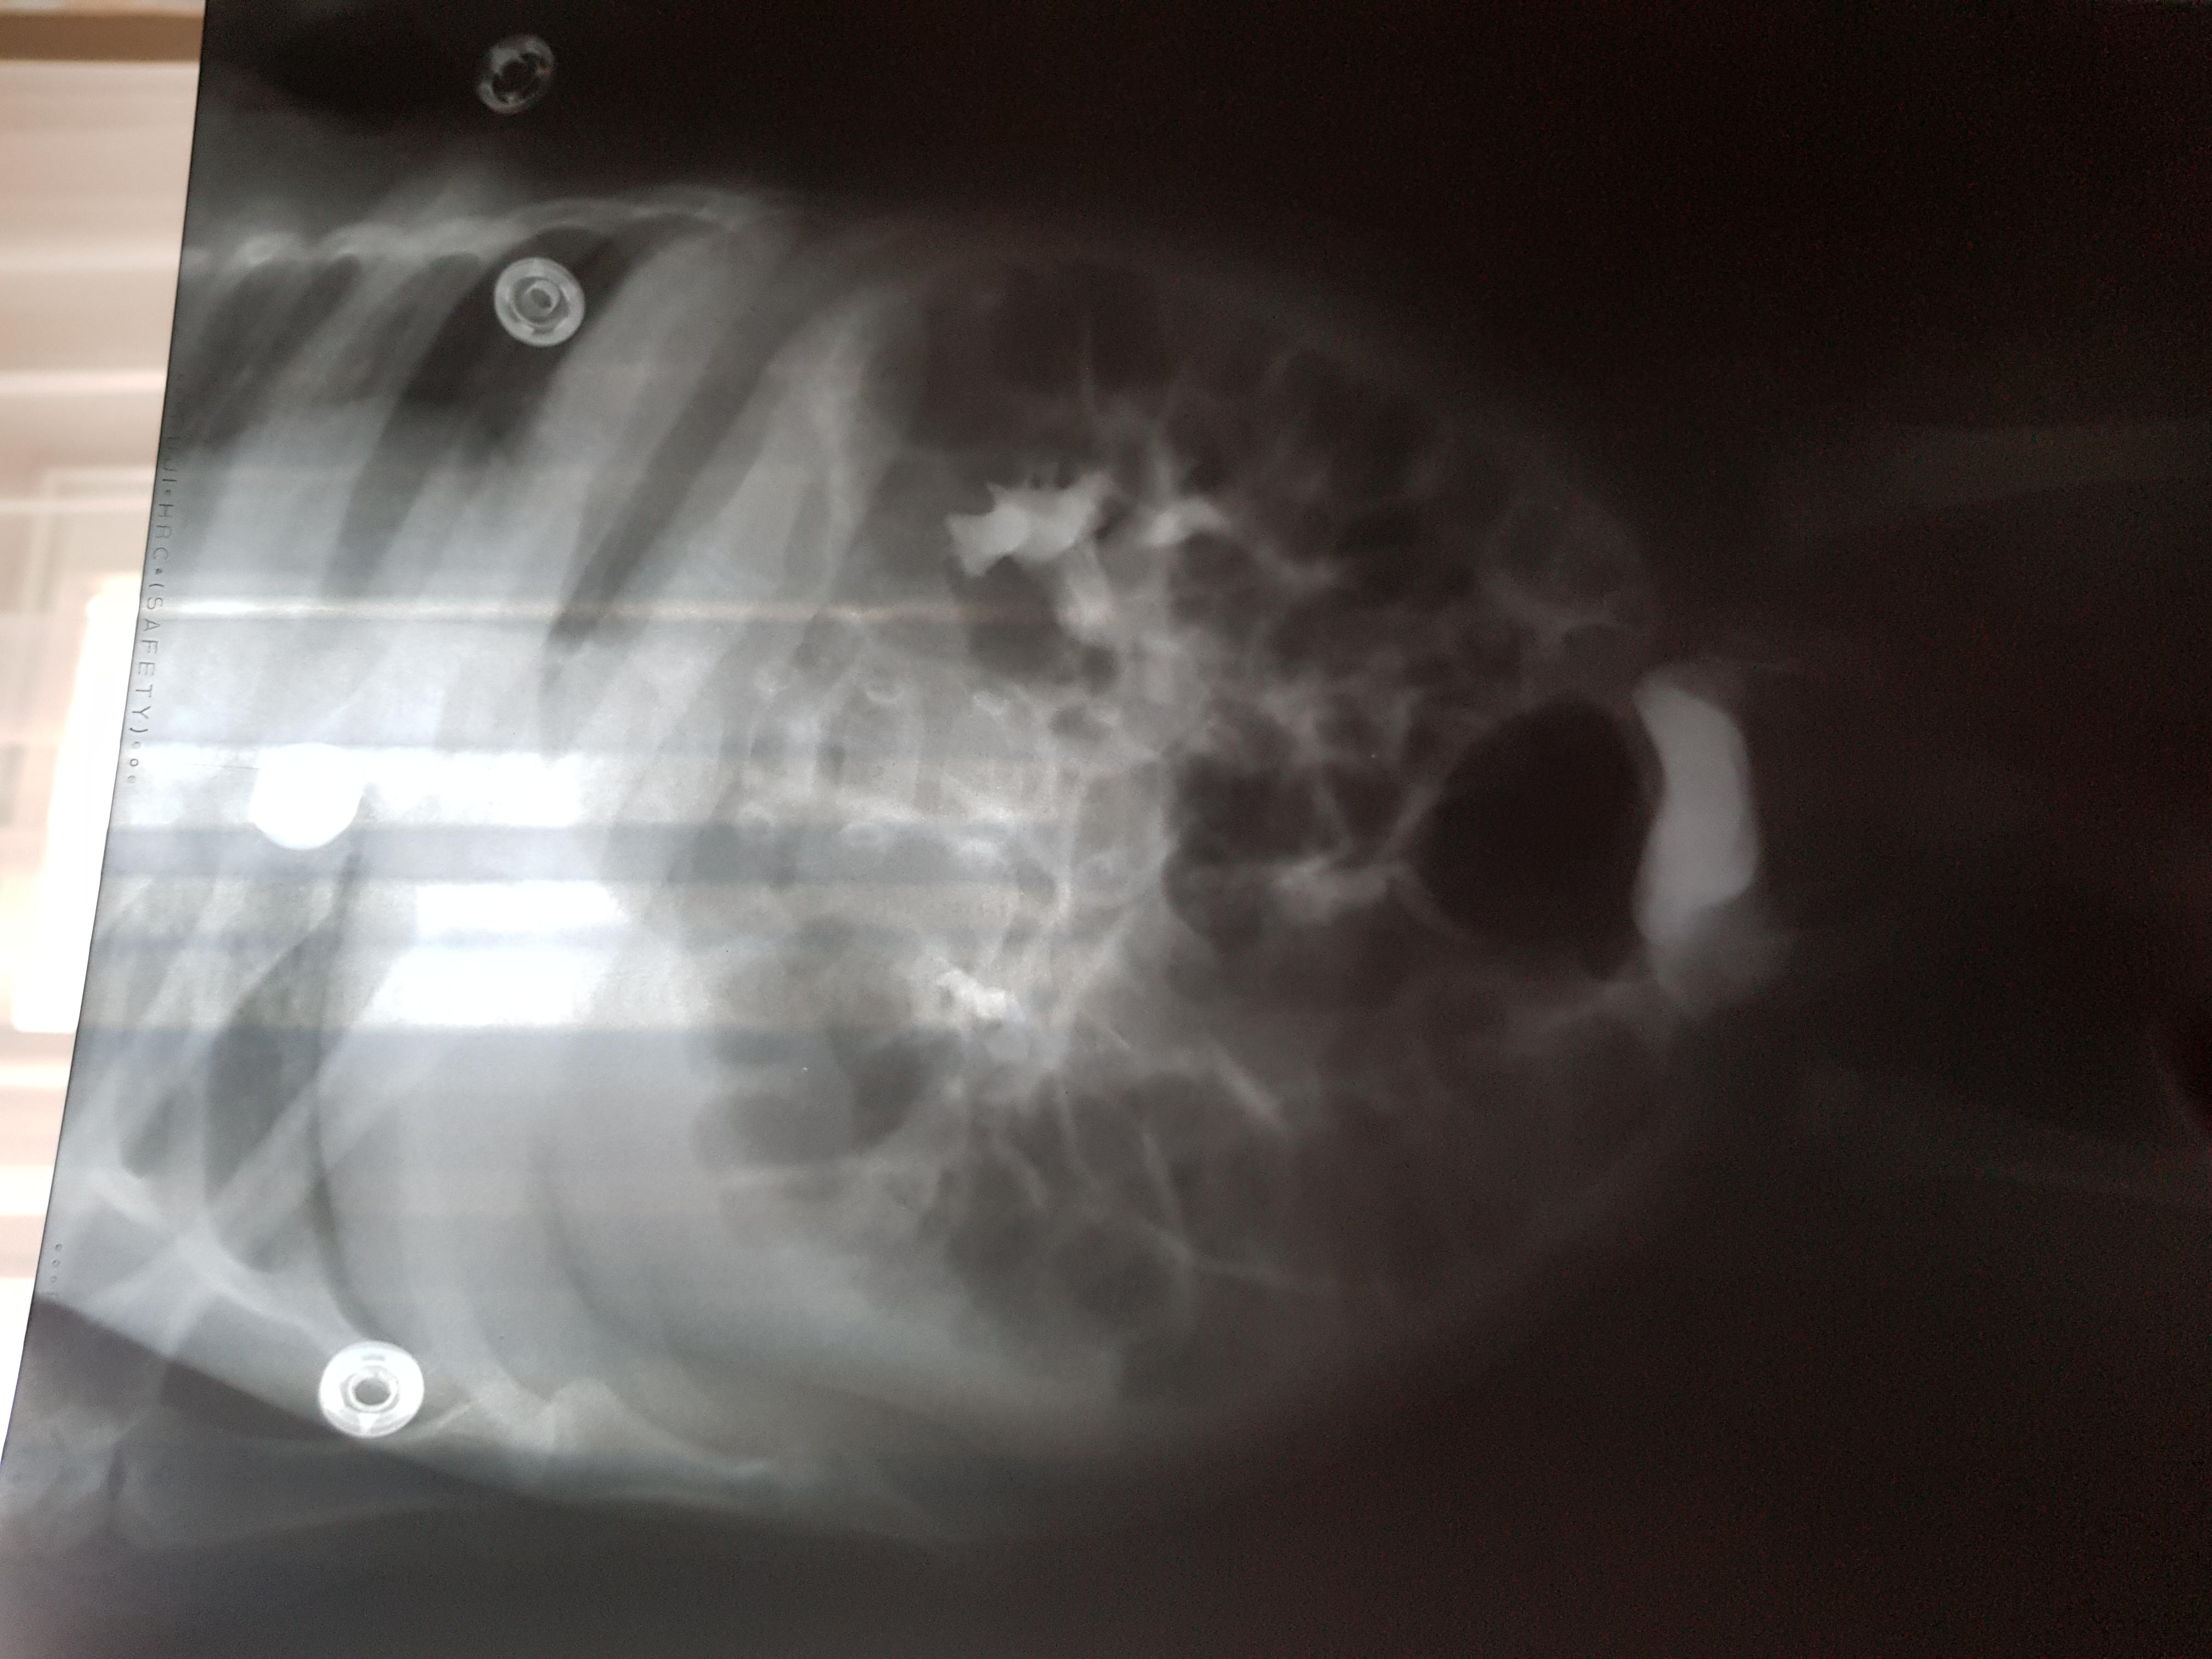

Болезнь Ормонда (ретроперитонеальный фиброз, забрюшинный фиброз) – хроническое воспаление жировой клетчатки забрюшинного пространства, которое постепенно приводит к компрессии и нарушению проходимости трубчатых структур данного анатомического участка. Чаще всего, в качестве этих тубулярных структур выступают мочеточники.

У меня есть сомнения, что причиной гидронефроза в Вашем случае явилось именно это состояние.

Возможно речь идет о пузырно-мочеточниковом рефлюксе.